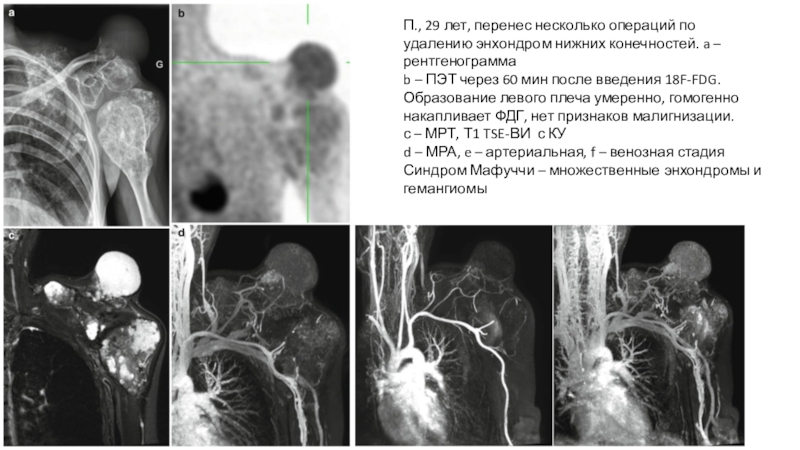

Слайд 23П., 29 лет, перенес несколько операций по удалению энхондром нижних

конечностей. a – рентгенограмма

b – ПЭТ через 60 мин после

введения 18F-FDG. Образование левого плеча умеренно, гомогенно накапливает ФДГ, нет признаков малигнизации.

с – МРТ, Т1 TSE-ВИ с КУ

d – МРА, e – артериальная, f – венозная стадия

Синдром Мафуччи – множественные энхондромы и гемангиомы

П., 29 лет, перенес несколько операций по удалению энхондром нижних конечностей. a – рентгенограммаb – ПЭТ через